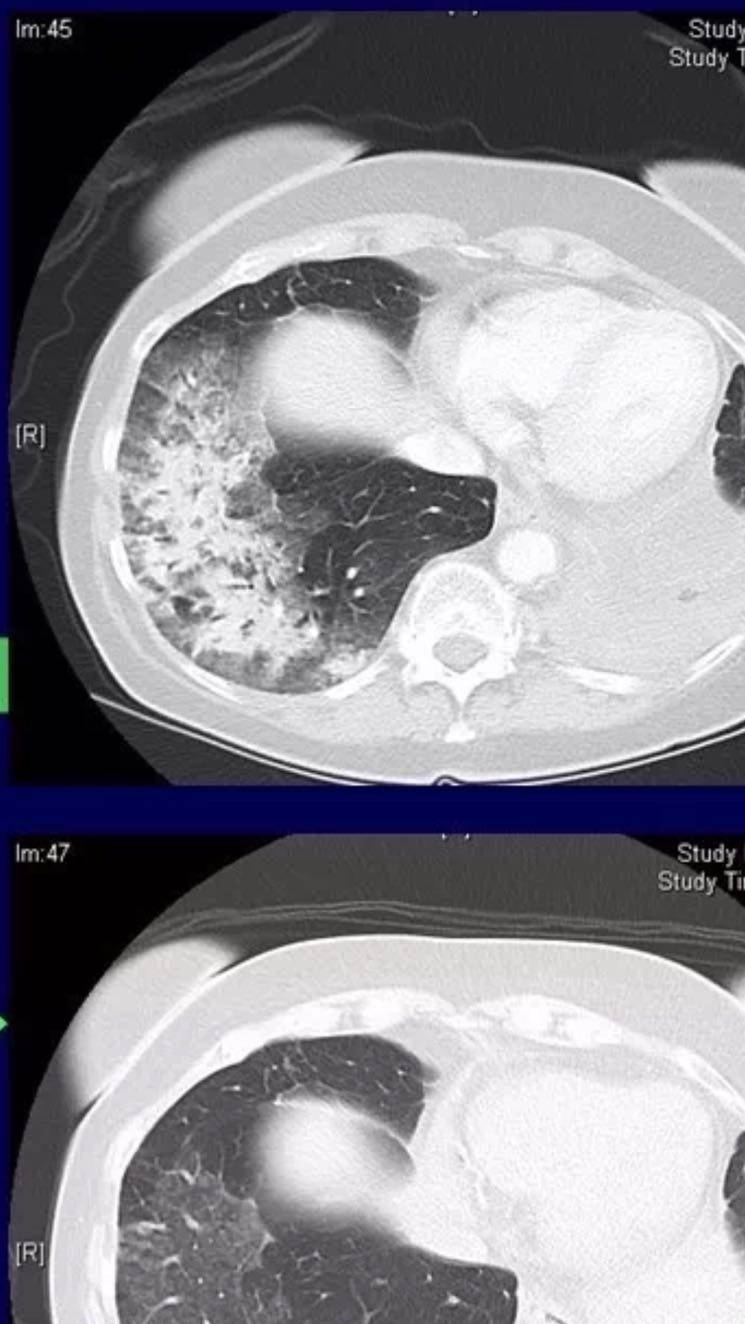

这是我母亲11月2日的片子

这是我母亲11月2日的片子 刚才的好像拍反了 我妈是左肺发炎的厉害

这是我母亲11月5日的片子

这是我母亲11月10日的片子 这是经过了激素没怎么用 因为市级医院倾向于细菌感染 他说激素大量用会影响抵抗力 只用消炎药和少量激素一个礼拜的效果

这是省级医生会诊后说是靶向药引起的间质性肺炎用激素冲后的一个礼拜的结果 陈医生您好 能不能从这些结果看是细菌感染还是靶向药引起的间质性肺炎呢

陈波医生行程中匆匆看了 片子的印象像靶向药引起的间质性肺炎,激素用了几天了